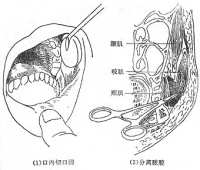

(3)选择型颈肌及神经切断术:(1981年)提出,不同类型痉挛性斜颈的头部姿势是各相关肌肉收缩构成的,而不是颈部全部肌肉参与的结果。手术治疗只需针对这些主要肌肉,没有必要切断双侧颈神经根和副神经根,以避免不必要的并发症。并提出,对旋转型斜颈可仅切除同侧的头夹肌和对侧的副神经;对后仰型斜颈,用手术切除左右部分斜方肌、头夹肌、头及颈半棘肌;对前屈型斜颈,可切断双侧副神经;对侧弯型斜颈,则做头弯向侧的头夹肌、肩胛提肌,个别病人如有同侧胸锁乳突肌的痉挛,也可加做副神经切断术。

(4)选择型周围神经切断术:此法主要切断颈神经根后支,切断的范围依据痉挛肌群多寡选择。其理由是所有颈后肌群全由颈1-7的神经后支支配。如果病情需要,可以一直切到颈7。该手术方法对旋转型斜颈有一定疗效。

(5)副神经根显微血管减压术:打开枕大孔及上颈段椎管。在手术显微镜下观察双侧副神经根周围有无血管对其压迫,通常压迫神经的血管是椎动脉、小脑后下动脉或脊髓后动脉,确认后切断该处齿状韧带,在神经与压迫血管之间垫入Tefleon绵,使之隔开。手术近期有一定效果,长期疗效尚待观察。

目前,根据患者临床表现及电生理检查来确定痉挛形式及受累肌群,个性化制定手术方案,在受到小儿脑瘫手术启发后,通过改良FD手术方式,取得明显效果,通过22例手术治疗,显效率为86%。